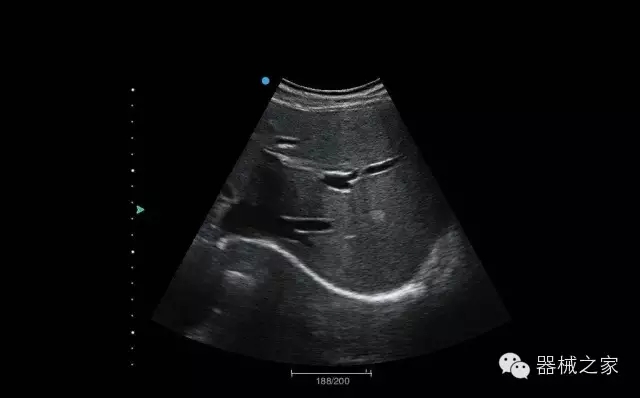

臨床圖片賞析

睪丸低速血流

臍帶血流

頸動脈頻譜